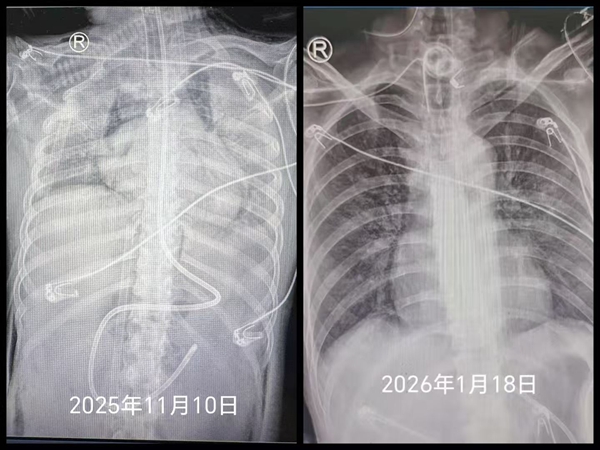

由于患者免疫力极度低下,快速锁定致病菌、精准施治成为遏制病情的关键。罗红教授带领重症肺炎MDT多学科诊疗团队,集结感染、影像、检验、临床药学等领域专家,围绕肺部影像分析、微生物筛查等核心问题开展十余次讨论,通过精准抗感染与免疫调节双重干预,让女孩肺部病灶逐步吸收,大白肺状态得到有效逆转。同时,针对女孩长期留置多重侵入性管路、院内感染风险高的问题,唐莉护士长带领护理团队建立每日感染风险排查清单,提前预判、尽早干预,实现多重管路留置期间零院内感染。

46天撤离ECMO,65天撤离呼吸机,72天实现简单交流,这场跨越两个多月的生命救援,是湘雅二医院现代医学技术与多学科协作能力的集中展现,也是22岁生命坚韧的见证,更是医者仁心的真实写照。